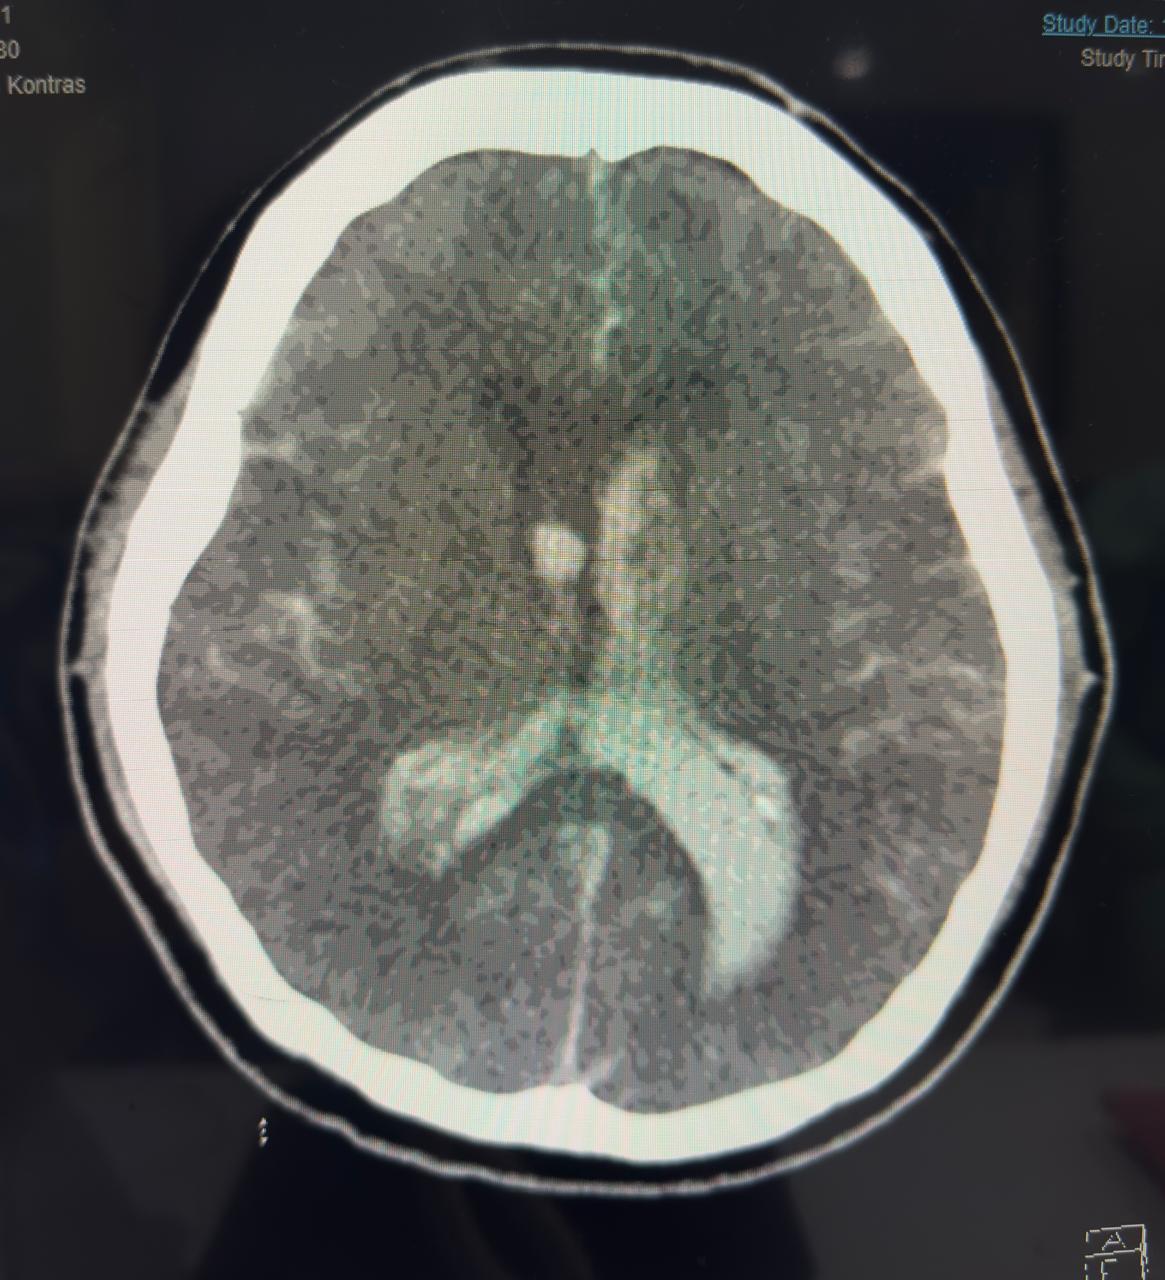

Second patient developed massive haemorrhagic stroke, despite normal APTT after PCI, anticoagulant use in normal dosage.

Both patient developed stroke periprocedural but in a paradoxical way. One with heavy thrombus burden young patient with thrombolytic, GP2B3A infusion, anticoagulation and dual antiplatelet but developed acute massive ischemic stroke and did not survive. The second patient developed acute massive haemorrhagic stroke due to sudden increase of blood pressure, despite the use of normal dose of anticoagulation, low ARC HBR score, and normal pressure during procedure. So stroke both ischemic or haemorrhagic are devastating and have high mortality, but until now there is no actual scoring system to predict only on ARC HBR to prevent bleeding periprocedural.